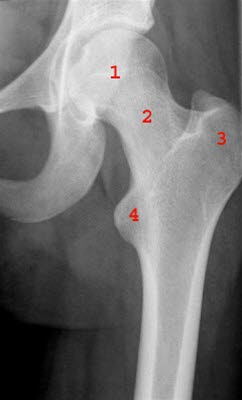

Diagnosen bekreftes ved røntgenundersøkelse av hofteleddet. Man ser da hvordan toppen på hoftekula glir av resten av leddhodet.

I de lange rørknoklene i beina og armene finnes vekstsoner eller vekstskiver der lengdeveksten i knoklene foregår. Denne vekstsonen betegnes på fagspråket for epifysen, og den befinner seg nær enden på et bein, det vil si nær leddet. I hoftekula på lårbeinet finnes en slik epifyseskive. I pubertetsårene kan vekstskiven svekkes og løsne fra benet, en såkalt epifysiolyse. Toppen av hoftekula (lårbeinshodet), som befinner seg ovenfor vekstsonen, begynner å gli bakover og nedover. Situasjonen kan sammenlignes med en softis som glir av kjeksen. Tilstanden må korrigeres raskt for å unngå livslange hofteplager.